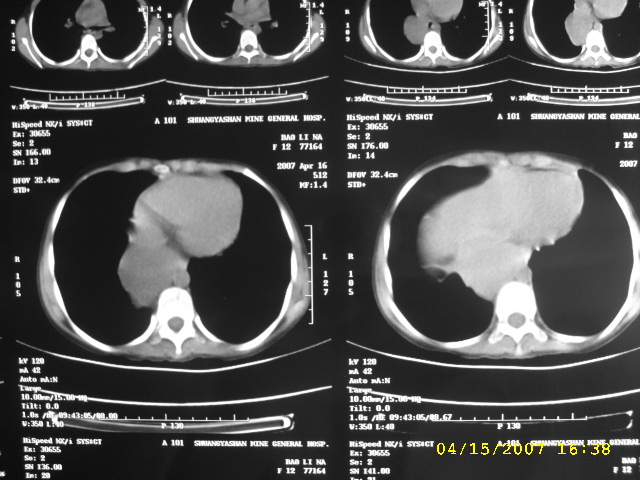

女,12,后纵隔占位十余年。

女,12,后纵隔占位十余年,没什么特异性,考虑1纵隔囊肿2肺隔离症3神经源性肿瘤,建议增强

女,12,后纵隔占位十余年,没什么特异性,考虑:1 纵隔囊肿. 2 肺隔离症. 3 神经源性肿瘤,建议增强

,12,后纵隔占位十余年,没什么特异性,考虑:1 纵隔囊肿[食管囊肿.  2神经源性肿瘤,3 肺隔离症.建议增强

考虑:1 支气管囊肿. 2 神经源性肿瘤;建议增强扫描。